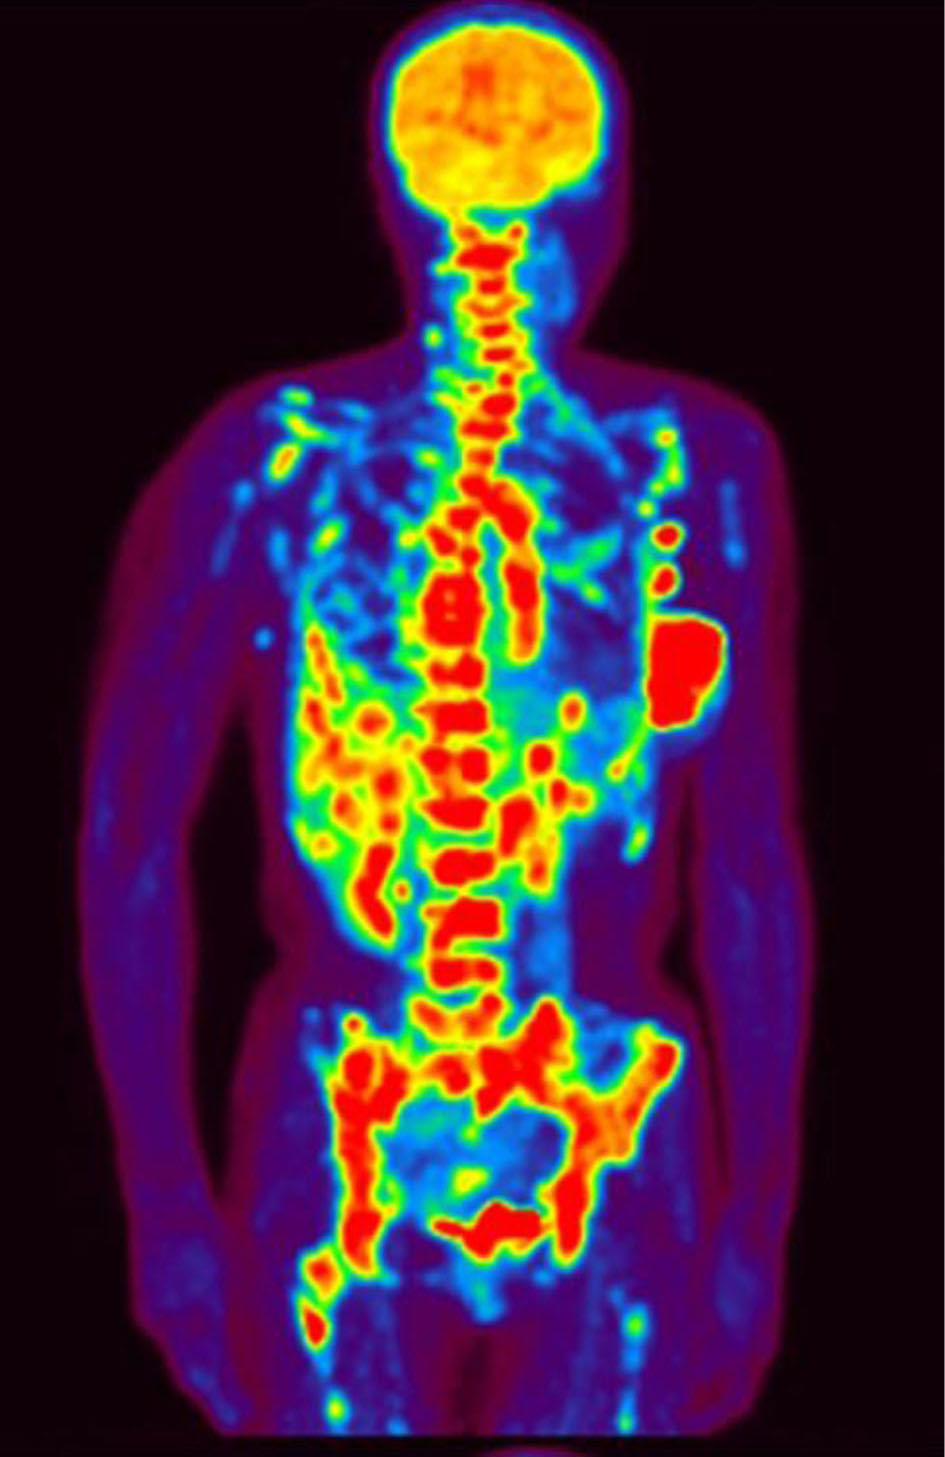

A 47-year-old woman presented at our hospital complaining of dyspnea upon physical exertion. A few weeks earlier, she had sought medical attention at another healthcare facility due to a persisting left breast tumor that had been present for 6 months. At that time, she was diagnosed with stage IV left-sided breast cancer (T3N3aM1; OSS, HEP, LYM). Pathology examination confirmed an invasive ductal carcinoma of the left breast with estrogen receptor (ER)- and progesterone receptor (PgR)-positive statuses, while human epidermal growth factor receptor 2 tested negative and showed a Ki67 index of 30%. The positron emission tomography showed multiple lymph nodes, bone, and liver metastases (Fig. 1).

![]() Click for large image | Figure 1. Positron emission tomography showing multiple lymph nodes and bone and liver metastasis. |